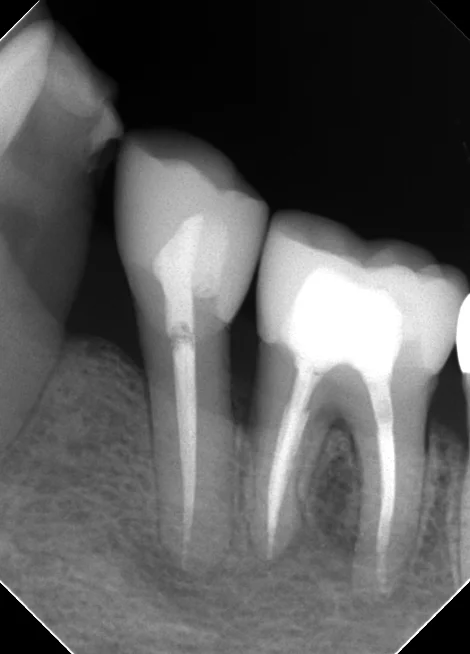

まずは術前のレントゲンです。

どちらも本来クラウン形態で治療すべきところを無理やりレジンにて治療されてしまっています。

青い部分がレジンで治療されたところなのですが・・・・一般の方が見ても、割れてしまって隙間だらけになっているのが分かるかと思います。

そしてその結果、本来は細菌が居ないハズの根管(神経の管の事です)内に細菌感染が生じて、根の先に大きく膿が溜まってしまっています。(赤い部分)

当然全く合っていない詰め物なので、食べカスは食事の度に歯に挟まり、歯周病も進んでしまっています。